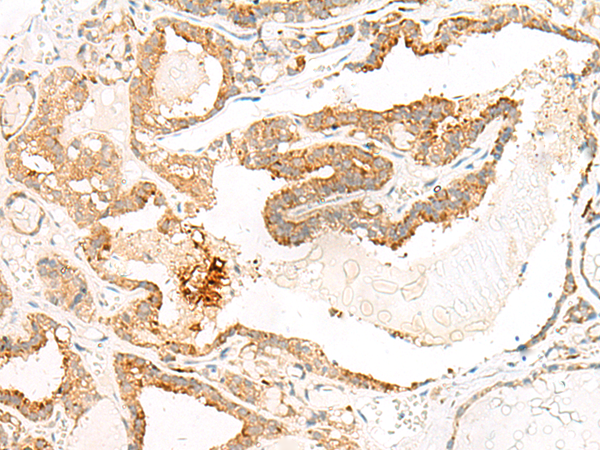

IHC positive control: |

Human cervical cancer and Human thyroid cancer |

IHC Recommend dilution: |

50-300 |